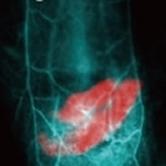

在产品应用方面,该公司的产品可应用于多个领域。例如小动物活体荧光全身、局部成像、荧光指导手术导航、血管成像、淋巴成像、肿瘤成像、炎症的检测与监测、药物追踪、活体原位疾病检测,药代动力学模型、药物疗效评价,生物发光、光热、光动力治疗等。其广泛的应用范围,满足了不同科研和医学实验的需求。

在产品质量和性能上,上海数联生物科技有限公司也有出色的表现。其荧光影像仪器产品有近红外二区宽场荧光成像系统、可见光区/近红外二区宽场双通道荧光成像系统、近红外二区显微成像系统,并开发了独特的近红外二区寿命荧光寿命成像系统,可应用于活体深组织定量监测。近红外二区成像平台对传统成像的穿透深度、空间和时间分辨率都有很大的提升。除了成像仪器,公司在近红外二区荧光探针的设计合成方面也具有独特的优势,其荧光探针产品包括有机荧光探针和无机荧光探针(稀土/量子点)以及探针表面功能化修饰。探针可针对不同的研究体系,在细胞、生物组织、小动物活体模型用于实时、高信噪比成像,也可通过设计实现对待测物的传感响应功能。此外,公司还承接科研实验服务项目,包括肿瘤、心血管、炎症、消化系统、可植入设备、肺功能、骨相关疾病、泌尿科、妇科、皮肤疾病等相关模型的建立以及成像监测等。